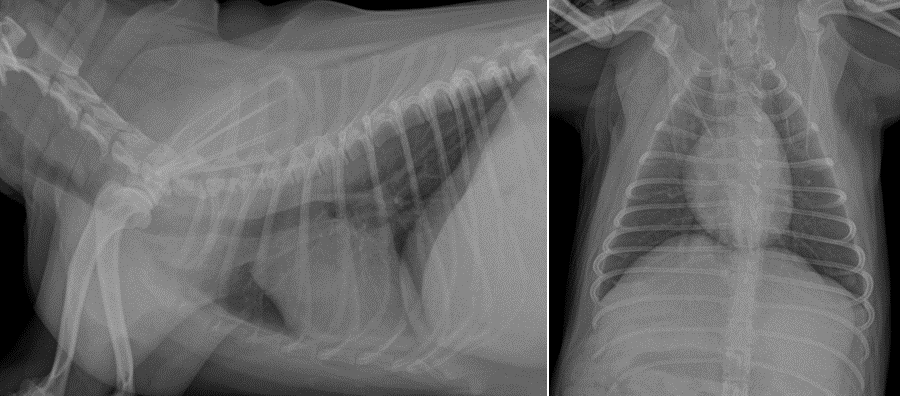

검사요크셔테리어 강아지 자궁축농증수술 I 부평 프라임 동물병원 ▶ 방사선 검사 환자의 정확한 상태를 확인하기 위해 화상검사를 실시하였습니다.

▶ 혈액 검사 마취 전의 컨디션을 확인하기 위해 혈액 검사와 흉부 방사선 검사를 실시했습니다.

▶ 방사선 검사